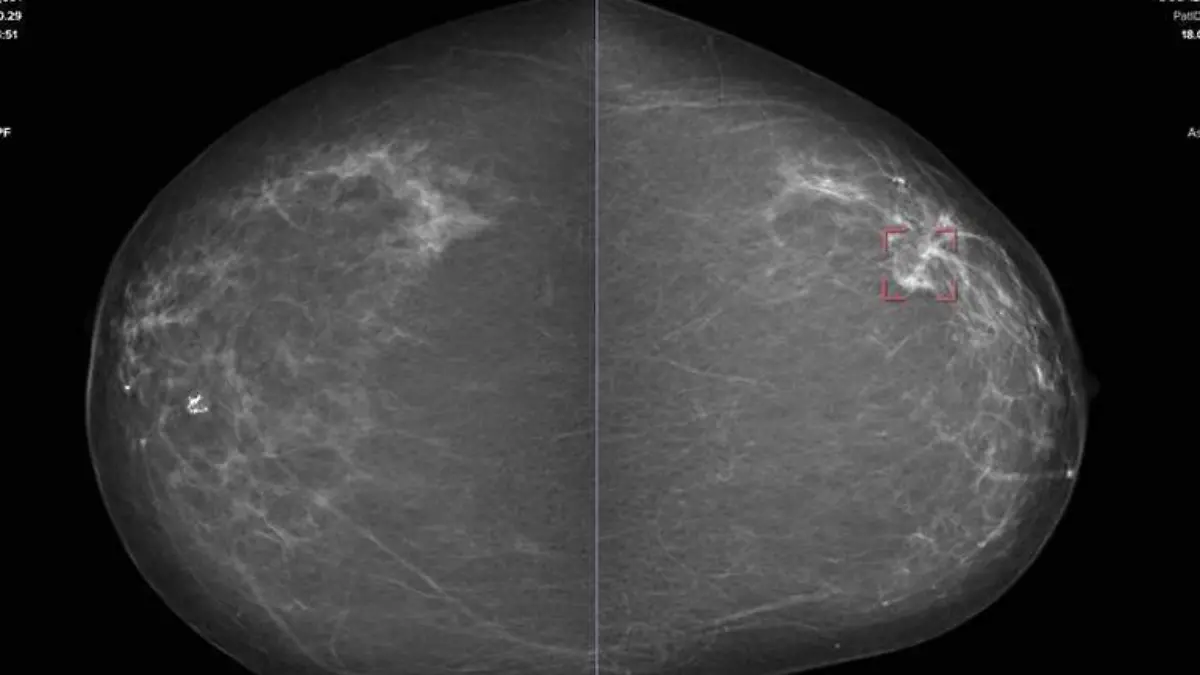

‘Caminata Rosa’, un llamado a la auto exploración contra el cáncer de mama

Este día el Hospital Regional “Dr. Juan Graham Casasús” organizó la 'Caminata Rosa' en el marco del Día Mundial de la Lucha contra el Cáncer de Mama